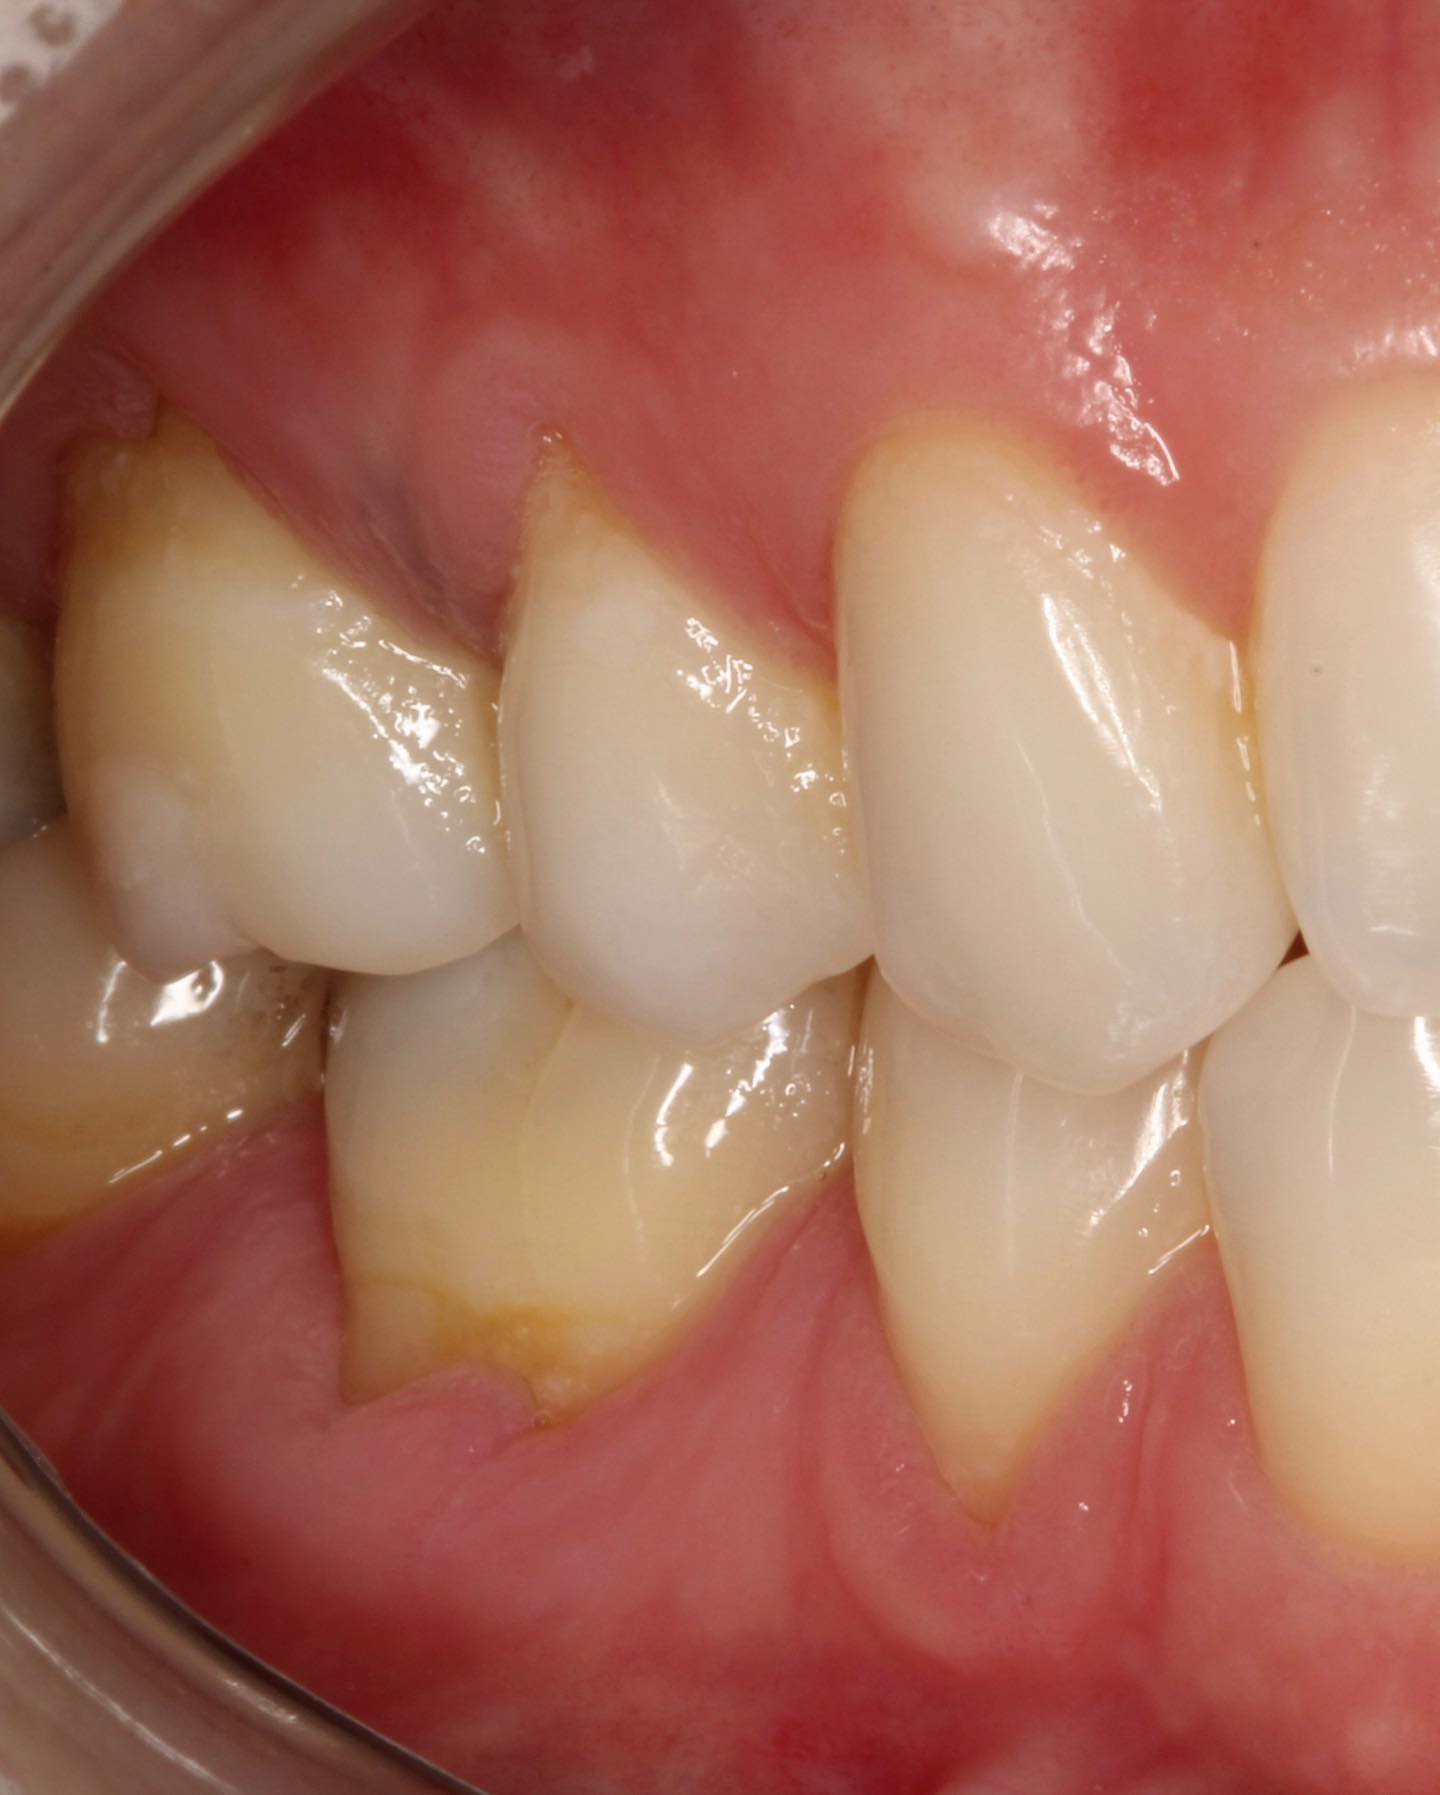

Connective Tissue Gingival Grafting for Gingival Recession